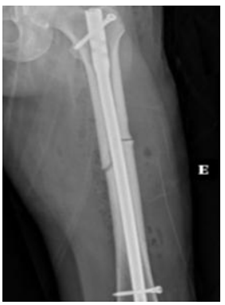

Você é residente da Clínica Médica e foi acionado/a para realizar interconsulta de uma paciente de 68 anos na Enfermaria de Ortopedia, após fixação de fratura de fêmur. Durante avaliação, paciente relata diagnóstico de osteoporose, e está fazendo uso regular de carbonato de cálcio, Vitamina D3 2000 UI/d e alendronato há 11 anos. Quando inquirida, ela nega quedas. Refere que estava realizando sua caminhada matinal no Parque do Utinga, quando sentiu uma dor intensa na face lateral da perna esquerda, momento em que procurou o Pronto Atendimento. Na avaliação bioquímica complementar, ela apresenta 25OHD de 42 ng/dL, níveis de eletrólitos, albumina, PTH e eletroforese de proteínas séricas normais. Após procedimento ortopédico, apresenta a seguinte radiografia:

Enunciado 4376376-1

Neste momento, a conduta prioritária é: